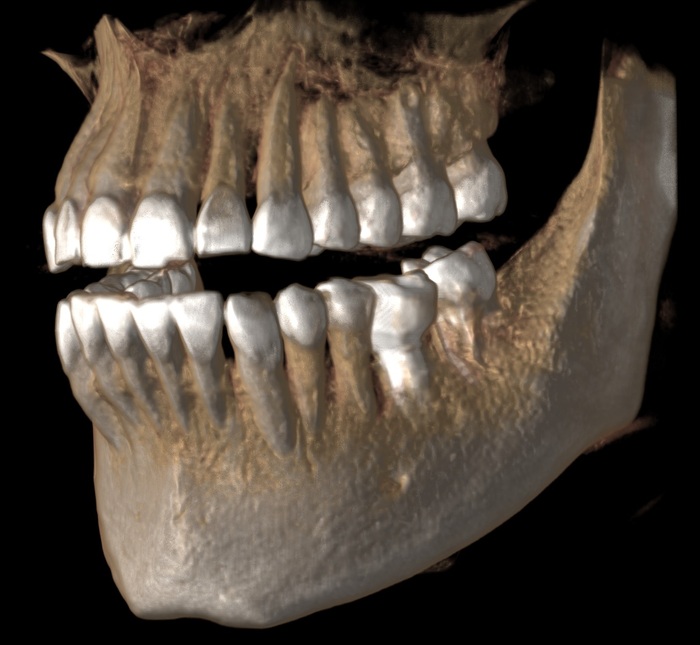

Ниже фрагмент компьютерной томографии, а интересующий имплантат справа снизу:

Увы, но рядом стоящий 7й зуб треснул пополам и было принято решение о его удалении и установке имплантата.

Для полной интеграции имплантата необходимо около 4х месяцев, но девушка пришла спустя 6, в июне 2018:

Жалоб нет, имплантат интегрирован. Следующим этом было снятие слепков и изготовление коронки. Ниже снимок от августа 2018:

Казалось, что все в порядке. Так, собственно, оно и было. Контрольный снимок в декабре 2019: